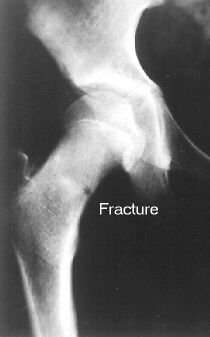

This 12 year old girl sustained a right femoral neck fracture by falling from a balcony(image 1). After 2 weeks of bed-rest, she was started walking with crutches. She completely returned to normal activities 6 months after the trauma. She was beginning to complain of the right hip pain 2 years after the trauma(image 2 & 3).

The large posterior surface of the femoral head remained intact therefore a base of the femoral neck osteotomy could be performed to rotate the femoral head forward and into valgus.